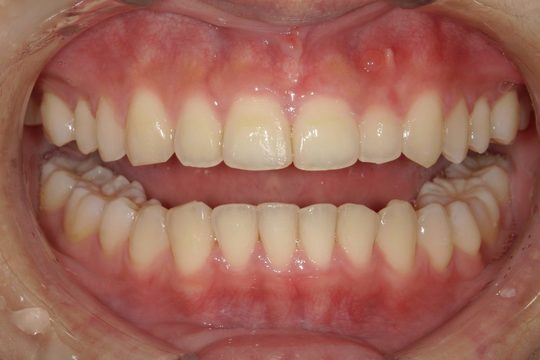

After

浜松市中央区・自動車学校前駅のインビザラインの症例

K.M 20代女性

上の前歯が前方に出ていて横顔が気になるとの主訴でご来院。上下犬歯から犬歯までの6本が噛み合うよう、全体的に歯を内側に移動させることで、前歯の噛み合わせを整え叢生と開咬を治療しました。

​治療の期間:R5. 7/5〜R7. 1/17

​治療の価格:66万円